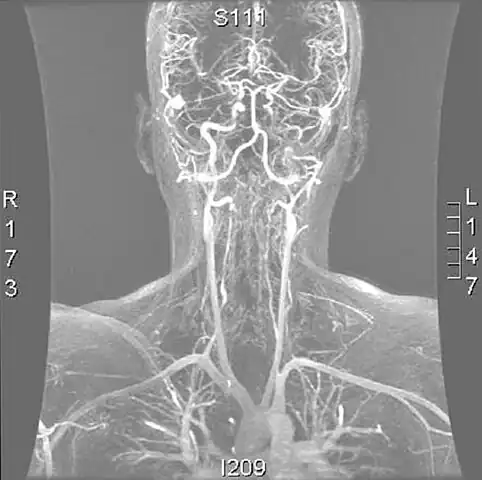

Cerebral vessels by brain MRA show cerebral atherosclerosis (and minor angiostenosis) -

Angio MRI of supra-aortic vessels after the injection of 20cc of gadolinium for contrast